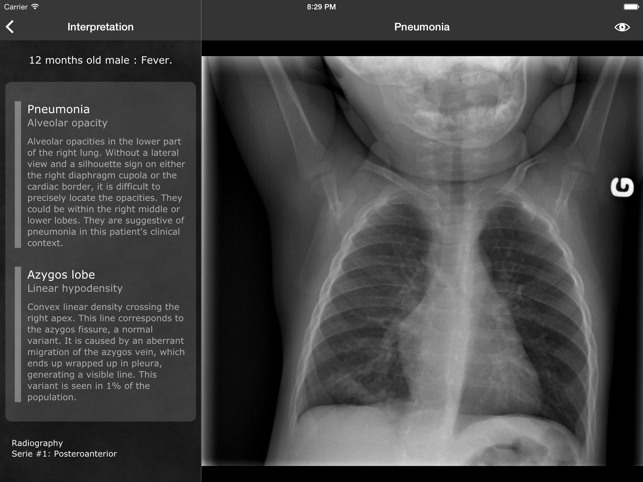

* Now compatible with iOS 8 *RealWorld Radiology is your ultimate guide to the basics of thoracic imaging. Learn to read chest X-rays in no time and discover the most frequent diagnoses through multiple fully annotated examples.RealWorld Radiology currently features more than 70 real-world cases (with more coming for free every month!) each containing: - High-resolution X-rays - All appropriate series (posterioranterior, lateral, expiratory, etc.) - Clinical information regarding the patient and mode of presentation- Detailed radiologic interpretation- Drawings of every radiological finding right on the X-ray Our cases have been especially selected for their high pedagogical value and real-world representativeness. They can be classified either by diagnosis (e.g. pneumonia, atelectasis, pulmonary fibrosis) or by actual radiological finding (e.g. alveolar opacities, interstitial opacities, silhouette sign), making the learning of the differential diagnosis easier than ever while keeping